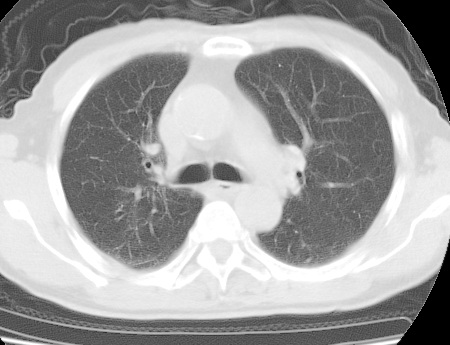

考虑右肺中叶不张,请大家发表意见

右肺中叶不张,中叶支气管开口不清,建议支气管镜检查。

中叶肺不张是没问题的,但为什么不在肺门区加薄扫呢?要查原因。

右肺中叶支气管闭塞,中叶肺不张,右侧肺门见肿块影。中心型肺癌的可能大。建议支气管镜检查。

右中叶体积明显缩小,且其支气管未显示,先考虑:中心型肺癌班右中叶肺不张。

建议:支气管镜检查。

(有病变的地方应该薄层扫描,方便于诊断)

中叶肺不张,肺门区加薄扫.

右肺中叶支气管狭窄,中叶不张,建议纤支镜检

平片就可以诊断右肺中叶不张,做CT就是要找原因!中叶支气管开口不清,建议支气管镜检查。